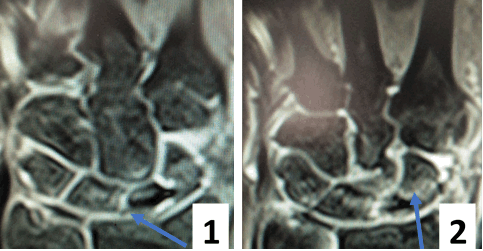

Результат МРТ правого лучезапястного сустава (рис. 2), подтвердил клиническое предположение о повреждении ладьевидно-полулунной связки, который заключался в нарушении целостности структуры связки. Также были выявлены признаки асептического некроза ладьевидной кости в стадии отека костной ткани.

Рис. 2. МРТ-исследование правого лучезапястного сустава. Получены протон взвешенные изображения с подавлением сигнала от жировой ткани (PD FAT SAT) в аксиальной, сагиттальной и фронтальной плоскостях, Т1 взвешенные изображения во фронтальной плоскости. На полученных сканах определяется: 1 – увеличение ладьевидно-полулунного сустава вдвое по сравнению с соседними; 2 – вдоль оси ладьевидной кости отмечается скопление жидкости, что можно расценить, как продольный перелом ладьевидной кости, либо отек костной ткани